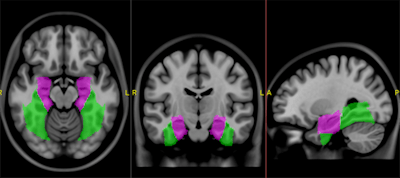

Still, the MNI 152 template played an instrumental role in the creation of the Gibby- Cvetko atlas, which also carries the name of co-developer Steve Cvetko, PhD, vice president at RIS/PACS firm Novarad. The researchers analyzed high-resolution images of 152 right-handed people with normal brains and modified the MNI 152 template to map standard cortical regions of the brain with 1-mm resolution.

"We tried to take the MNI 152 dataset and obviate the need to map back into the Talairach coordinates and create a new atlas based on that dataset," W. Andrew Gibby said. "To do this, we subdivided the idealized brain from the MNI 152 template and used manual demarcation of the cortical regions, which were subsequently segmented using prescribed algorithms to subtract white matter, eliminate overlapping, and ensure that all gray matter was covered."

With the addition of automated scalp stripping and deformable autoregistration, the researchers segment both control data and patient images to compare anatomic areas of the brain. Real-time interaction with the brain atlas also allows physicians to locate activity at any time.